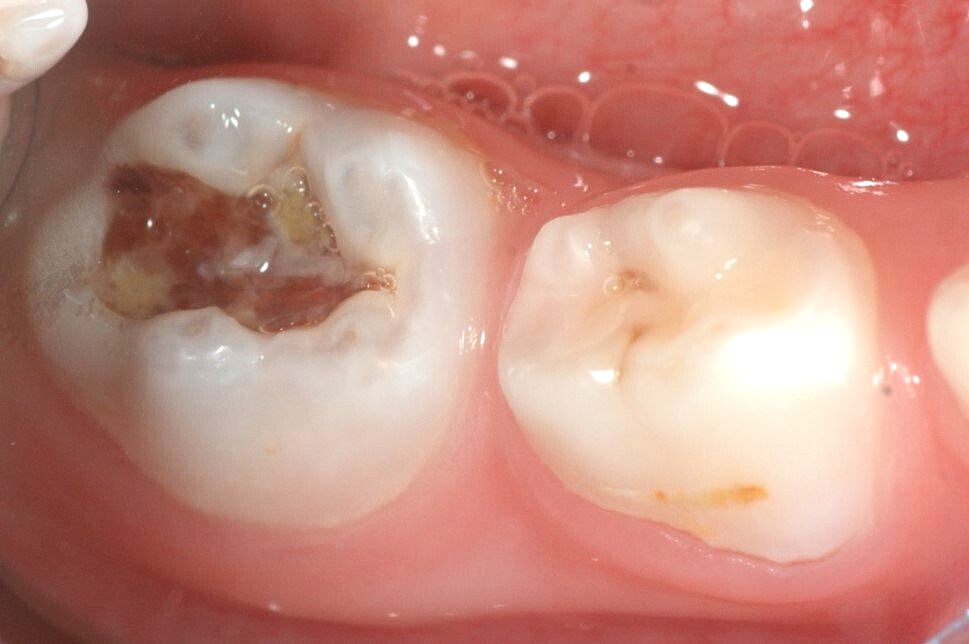

Schritt 1: Stark kariöser Milchbackenzahn